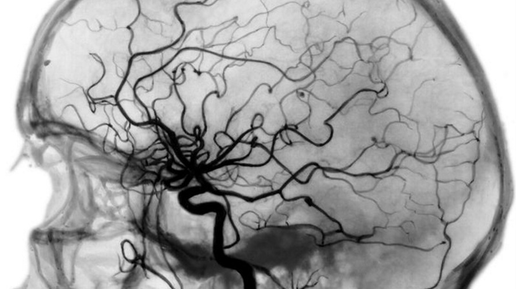

Если вы говорите себе «у меня АД всегда 150/90 мм - и это моя норма», вы играете в скверную игру против собственных сосудов. Термин «рабочее давление» звучит уютно, даёт чувство контроля и оправдывает бездействие. Проблема в том, что ваши сосуды не знакомы с этим словом. Для них важны только две вещи: насколько высоко ваше давление и как долго оно остаётся высоким. Этот крайне вредный миф, распространенный еще в советских поликлиниках, держится на трёх опорах. 1. Первая - адаптация. Годы с повышенным давлением смещают настройки ауторегуляции кровотока в мозге и других органах...